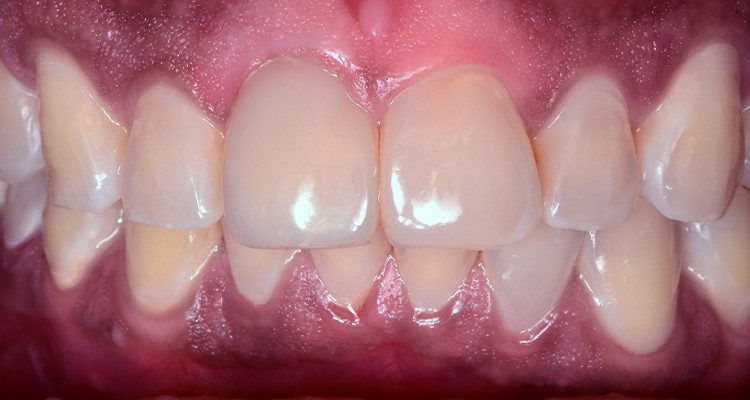

2 | Imagem intraoral frontal da arcada superior.

QUEIXA PRINCIPAL: Insatisfação estética do sorriso com envolvimento de forma e cor nos dentes 11 e 21.

Ao procurar atendimento clínico, foi verificada restauração extensa no dente 11 devido a alteração de cor da resina composta associado à restauração insatisfatória.